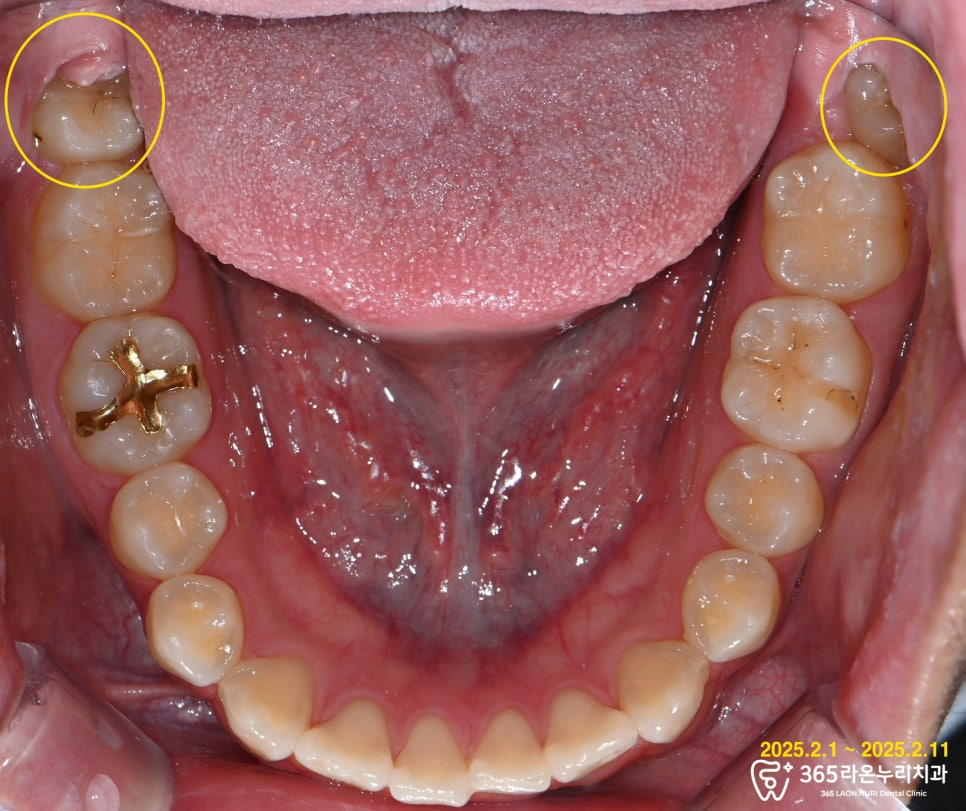

해당 환자의 구강 사진을

보시면 사랑니 주변으로

잇몸이 부어 있는 양상을

확인할 수 있습니다.

위턱에도 매복된 치아가 있지만

당장 통증이나 불편한 점은

없었기에 다음 번에 발치를

진행할 예정에 있습니다.